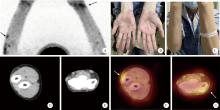

经典型Sweet综合征 18F-FDG PET/CT多脏器异常显像1例

Classical Sweet syndrome with multiple organ lesions by 18F-FDG PET/CT: A case report